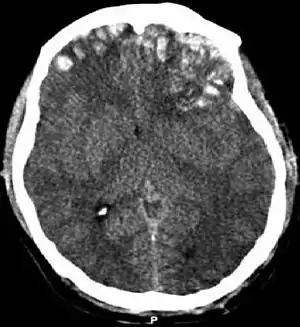

Movement disorders that may develop after TBI include tremor, ataxia (uncoordinated muscle movements), spasticity (muscle contractions are overactive), myoclonus (shock-like contractions of muscles), and loss of movement range and control (in particular with a loss of movement repertoire).[31][33] The risk of post-traumatic seizures increases with severity of trauma (image at right) and is particularly elevated with certain types of brain trauma such as cerebral contusions or hematomas.[34] People with early seizures, those occurring within a week of injury, have an increased risk of post-traumatic epilepsy (recurrent seizures occurring more than a week after the initial trauma).[35] People may lose or experience altered vision, hearing, or smell.[24]